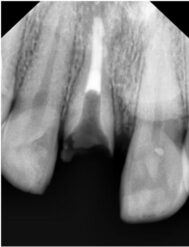

Realizamos radiografía panorámica y periapical de la zona, donde podemos observar que le queda un resto radicular, el cual presenta una gran infección periapical, parece llevar intraconducto un material intraconducto y una obturación provisional sobre el mismo. Esta obturación provisional está completamente suelta y filtrada.

- Apicoformación con MTA del resto radicular que presenta para la formación de un stop apical y su posterior tratamiento endodóntico con técnica de obturación termoplástica.

Procedemos a la realización del tratamiento conservador. Empezando por la apicoformación, endodoncia y restauración del diente. A continuación podemos ver una sucesión de radiografías con la evolución del tratamiento del paciente y la intervención realizada.